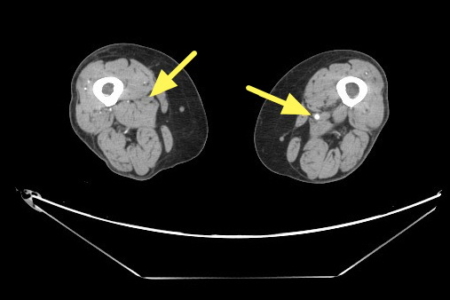

楊凱迪診治一位64歲長期洗腎的女性患者,數月來反覆出現下肢刺痛,夜深與洗腎後特別明顯,同時右小腿與腳踝各有一處約3×5公分久未癒合的慢性傷口。整形外科醫師清創時發現傷口幾乎沒有出血,轉介心臟血管外科,經「踝臂血壓指數(ABI)檢查」左右腳分別為僅約0.67及0.64,代表下肢血流循環不良。電腦斷層血管攝影更顯示雙側股動脈及膕動脈嚴重狹窄。

與患者溝通後,決定採行「微創導管血管內介入治療」,目前的血管內治療,除了常見的血管內氣球擴張與支架放置,亦可使用「機械式除栓裝置」,清除血管壁上的鈣化斑塊。搭配「血管內超音波(IVUS)」提供斑塊的即時三維影像,協助醫師精準定位斑塊方位。